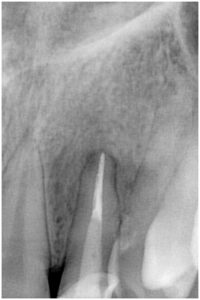

症例2

3ヶ月後